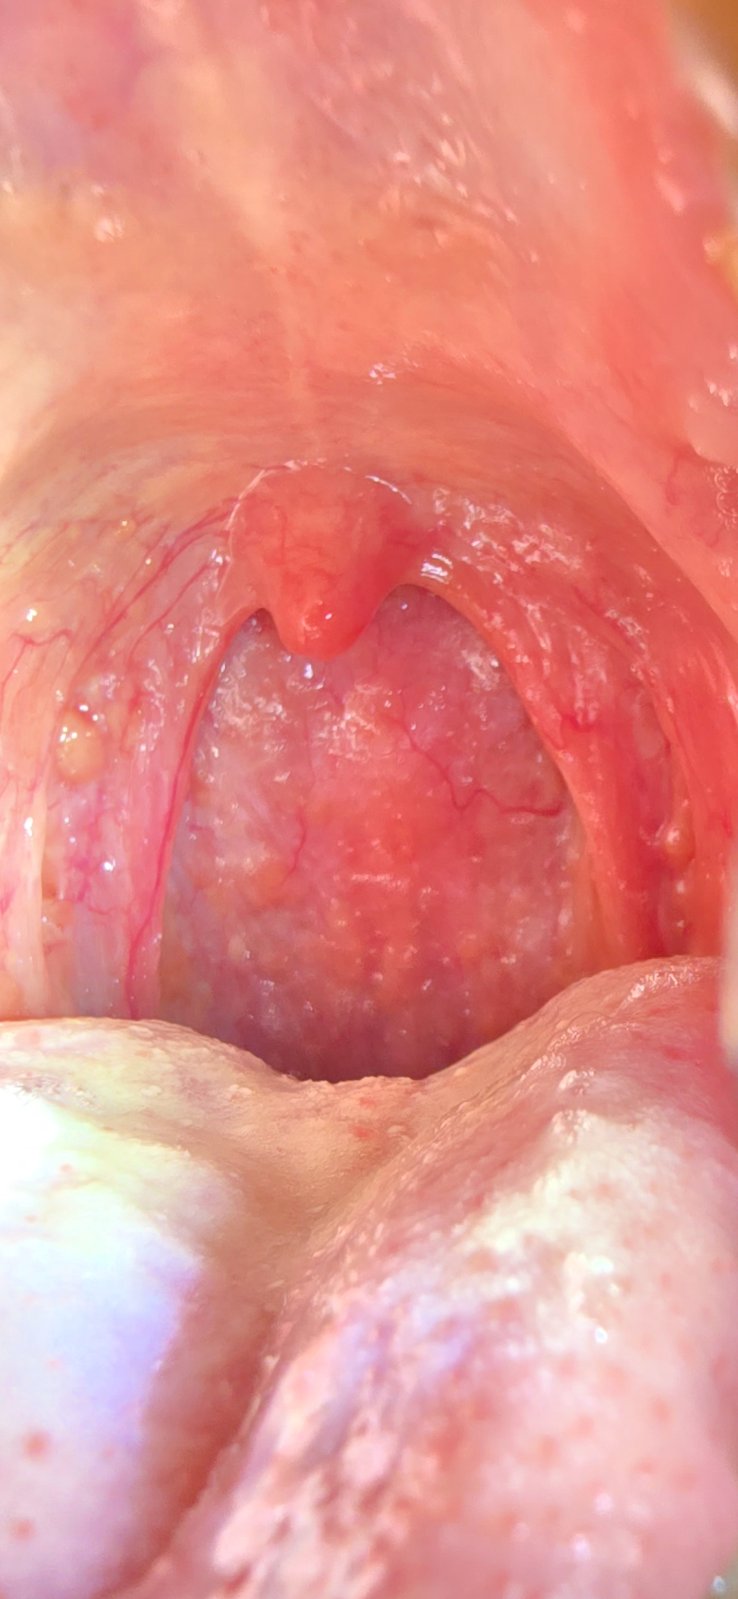

Ahojte už dlho mám v hrdle taká žlté divne pľuzgieriky. Hrdlo má aj pravidelné boli. Teraz som mal nedávno chorobu, silný zápal hrdla a dutín. Bral som ATB. Lekárka pozerala hrdlo. Ale pľuzgieriky tam boli už pred tým. Teraz mám pocit že ich je ešte viac. Viete podľa foto čo to môže byť. Tá jedna na ľavo žltá hrudka už dosť veľká. Začínam sa báť. A vzadu na stene v hrdle tiež sú dosť len menšie. A dosť mám aj zápach z úst dlhodobo. A stále sa mi robí biely povlak na jazyku. Mám 31 rokov a som dosť športovo založený. 70 Kg

@domino25 neviem, ale tie pľuzgieriky by som pripisala ATB tiež som ich mala po ATB ale boli číre, na biely povlak použi škrabku na jazyk